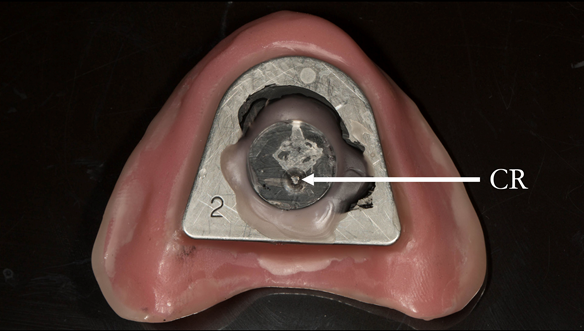

This newsletter describes in step by step detail Anne's transition from an immediate complete upper denture to a definitive complete upper denture.

The clinical situation and treatment process is shown in detail below with photographs. In addition, threre is a link to the a 45 minute webinar I gave explaing this case. I provided the clinical work and Rowan Garstang provided the technical work.